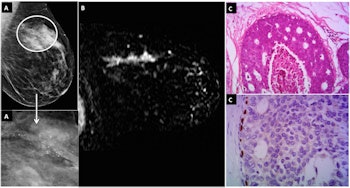

A: Mammograms with digital magnification of side profile view featuring pleomorphoic grouped microcalcifications (highlighted areas) at the left breast at junction of the upper quadrants, BI-RADS category 4B. B: MRI: Axial T1 sequence following administration of contrast agent with image subtraction displays linear and heterogeneous nonmass lesion enhancement (arrow) in the topography of microcalcifications observed on mammogram, BI-RADS category 4C: Histological sections showing solid neoplastic proliferation, increase in nuclear size and restriction to the duct, compatible with intermediate nuclear-grade DCIS. Images courtesy of Dr. Gustavo Machado Badan.